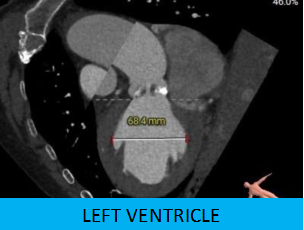

患者:老年男性,因发作性胸闷咳嗽2年,加重伴晕厥10余天收治入院,超声心动图显示主动脉瓣重度钙化增厚,回声增强,开放受限。平均跨瓣压差 48mmHg,最大压差84mmHg,瓣上速度 4.77m/s,EF32%,提示主动脉瓣重度狭窄并伴有轻度关闭不全。

1.主动脉瓣瓣环周长90.9mm,平均周长径28.9mm。